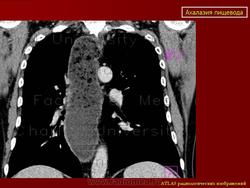

Ахалазия.

Ахалазия